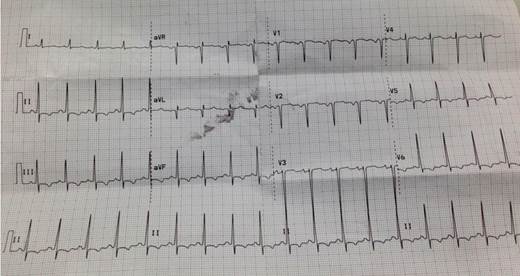

Sexo femenino, 40 años, procedente de Danlí - El Paraíso (Honduras), obrera, casada. Sin antecedentes personales de valor patológico. 3 Gestas, 3 Partos, 3 Hijos vivos. En octubre 2015, tras embarazo de 38 semanas sin complicaciones, se indujo el trabajo de parto en elInstituto Hondureño de Seguridad Social (IHSS) de Danlí, por diagnóstico de preeclampsia leve, sin ninguna complicación. Alta a domicilio. Comienza 2 meses luego del parto con disnea de esfuerzo progresiva, disnea de reposo y ortopneauna semana previa a la hospitalización. En enero 2016 es evaluada IHSS en Tegucigalpa destacándose al examen físico: paciente lúcida, presión arterial 90/70mmHg, frecuencia cardiaca 115 latidos/minuto,saturación oxigeno 94%, frecuencia respiratoria 22/minuto, temperatura 37 °C. Examen cardiovascular: choque de punta visible y palpable en sexto espacio intercostal izquierdo línea axilar anterior. Ritmo regular. Primer ruido de intensidad disminuida, sin desdoblamiento. Silencios libres. Crepitantes basales bilaterales. Ingurgitación yugular, edema de miembros inferiores bilaterales. Estudios principales: Hemograma: hemoglobina 13.3 g/dl, hematocrito 41.6%, plaquetas 218.000/mm3, leucocitos 10.900/mm3. Creatinina 1.0 mg/dl. Sodio 137mmo/L, AST 175 U/L, ALT 350 U/L, colesterol total 263.14 mg/dl, triglicéridos 272.19mg/dl, Hormona estimulante de tiroides: 3.03 u/ml, serología por Chagasnegativa.Radiografíade tórax (Figura 1) y Electrocardiograma (Figura 2): Ritmo sinusal, frecuencia cardiaca 100, eje normal, PR 0.12, QRS 0.08, con depresión asimétrica del ST y onda T invertida en II, III, AVF, V4,V5, V6.

En la radiografía de tórax se encontrócongestión venosa pulmonar y cardiomegalia. En el electrocardiograma había taquicardia sinusal y alteraciones en ST y onda T. También es posible hallar hipertrofia ventricular izquierda, eje izquierdo desviado, bloqueos de rama, fibrilación auricular 1 3 5). El “gold estándar” es el ecocardiograma, donde se buscadisminución de la fracción de eyecciónyla presencia de hipertensión pulmonar8,12).